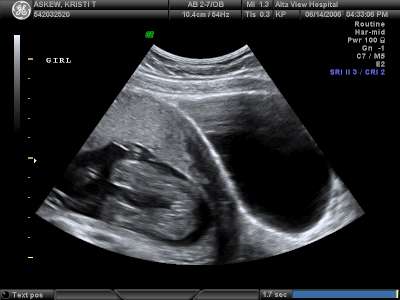

It's a GIRL!!

When we went in for our ultrasound, the radiology technician put the ultrasound device on Kristi's belly and immediately was shown our little girl's girly parts. Dan and Kristi were both glad she wasn't being modest. The rest of the ultrasound was even that much better knowing she was a she.